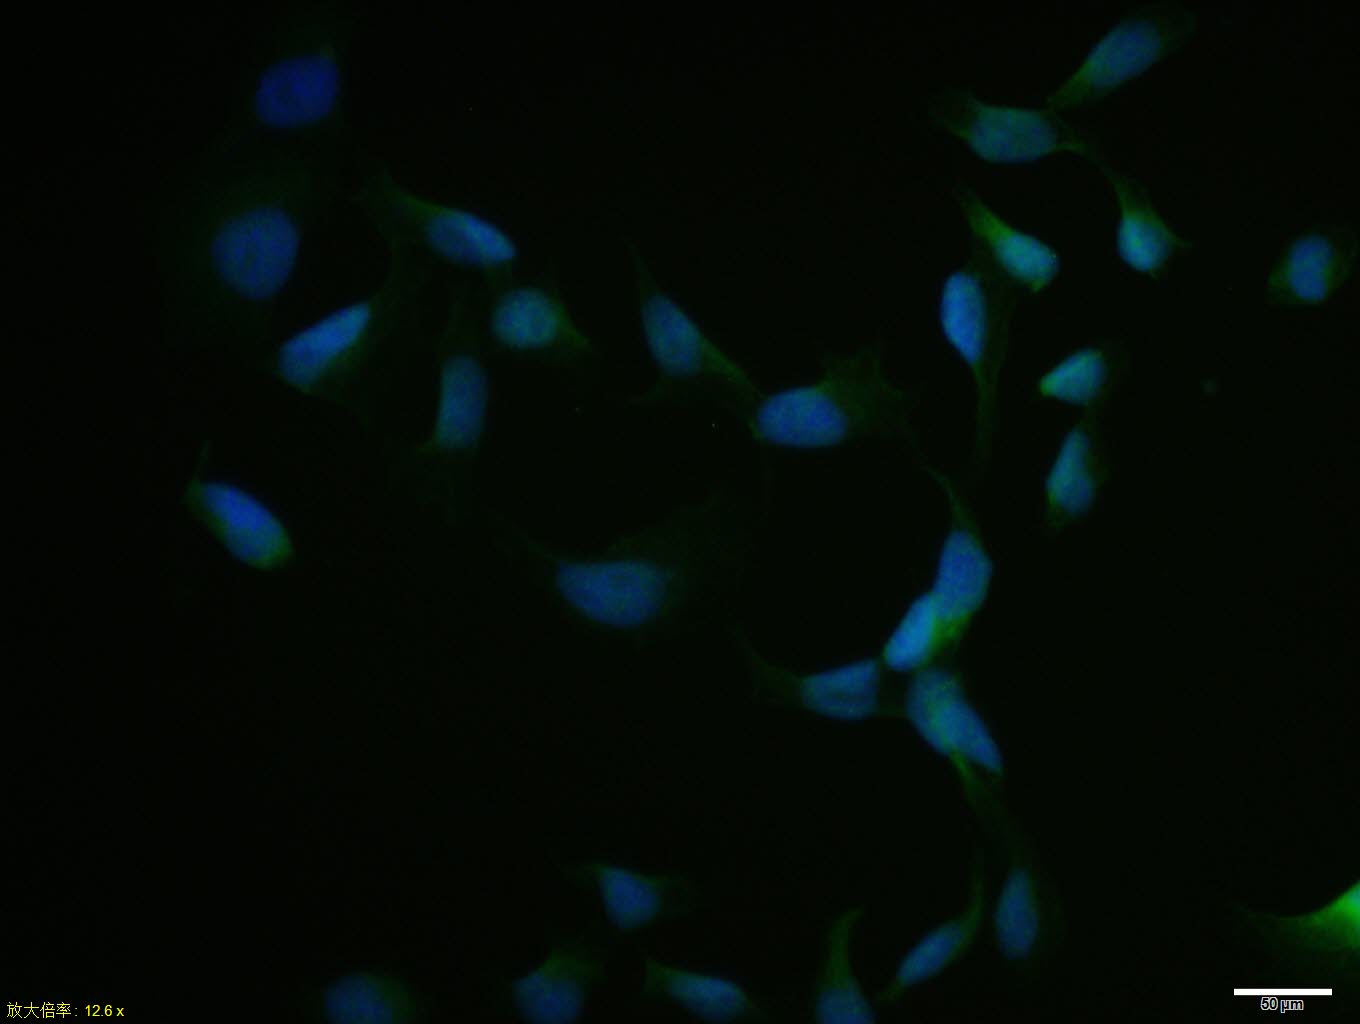

Hela cell; 4% Paraformaldehyde-fixed; Triton X-100 at room temperature for 20 min; Blocking buffer (normal goat serum, C-0005) at 37°C for 20 min; Antibody incubation with (NRF1) polyclonal Antibody, Unconjugated (bs-1342R) 1:100, 90 minutes at 37°C; followed by a conjugated Goat Anti-Rabbit IgG antibody at 37°C for 90 minutes, DAPI (blue, C02-04002) was used to stain the cell nuclei.